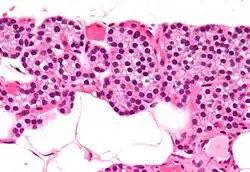

Célula principal da paratiroide

As células principais da paratiroide são células das glândulas paratiroides que produzem o hormônio da paratireoide.